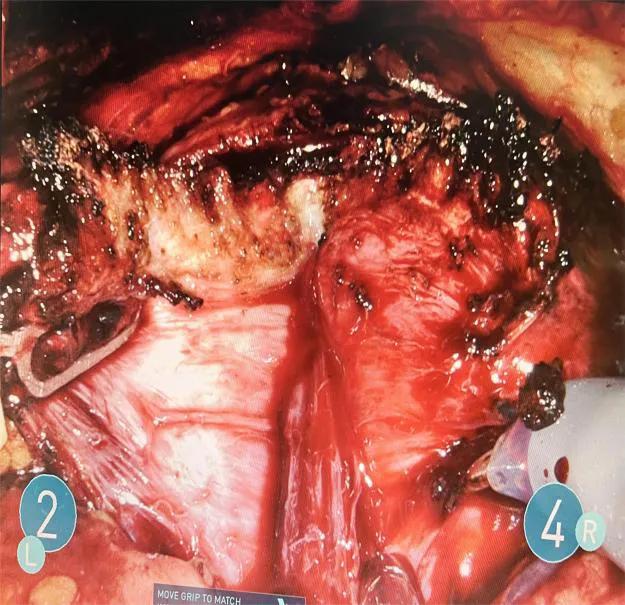

林先生(化名),年过古稀,近期一直遭受尿潴留的困扰已有3个多月。他一直备受前列腺增生的困扰,由于长期携带心脏起搏器的原因,频繁就医于各个医院。最终,他决定不惜长途跋涉,亲自到哈尔滨医科大学附属第一医院,希望能够得到泌尿外科二病房主任王春阳教授团队的治疗。入院后,经过全面的检查,医生了解到林先生的前列腺大小约为161克。考虑到患者前列腺体积巨大的情况,王春阳教授团队与患者及家属进行了详细讨论和沟通后,最终决定采用机器人辅助的单孔Madigan手术治疗方式。尽管患者存在多种基础疾病,手术难度极高,风险较大,但在王春阳教授、贾光教授娴熟的手术技巧和精湛的团队支持下,麻醉医生吴进荣教授和手术护士李晓冬、王久亮的大力支持下,手术顺利完成。王春阳教授团队成功完整地切除了大小约7.0cm * 7.0cm * 6.0cm的前列腺组织,手术仅持续了111分钟,术中出血量仅为45毫升。术后,患者恢复情况良好,未进行常规膀胱冲洗,每天引流液量不到20毫升。在术后的第4天,成功拔除引流管,并且平稳安全地出院。

切除增生的前列腺腺体